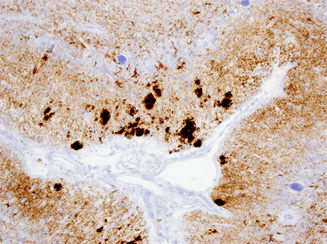

大脳皮質神経細胞におけるGFRα1の発現(左がアルツハイマー病例、右がコントロール例。黄色の矢印はGFRα1抗体でラベルされない神経細胞を示す)